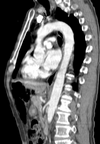

How well did you know this?

1